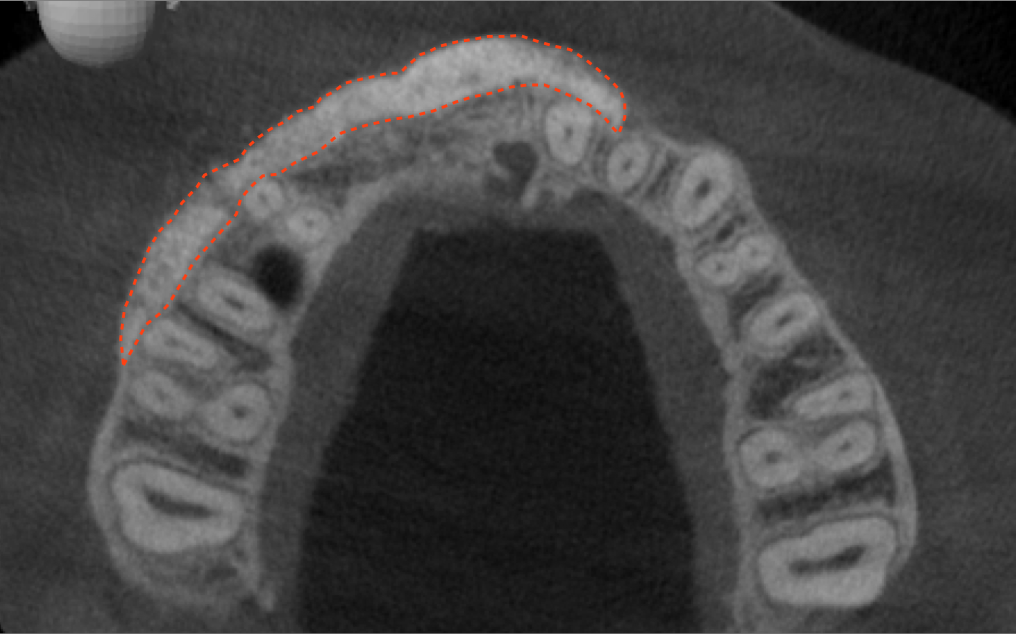

Tomographic images revealed a large tridimensional defect, with vertical and horizontal loss of bone extending to the apical third of teeth Nos. 6 and 8. Additionally, a buccal bone dehiscence was evident on tooth No. 5, and thin labial plates secondary to the orthodontic movement were present in several areas (Figure 3 and Figure 4).

Because recession was already present on tooth No. 5, the scope of the SMART procedure was extended to horizontally augment adjacent areas that exhibited dehiscences and thin buccal plates (Figure 16). The augmented areas evident in Figure 16 (which can be compared to the preoperative imaging in Figure 4) were accomplished using two remote incisions. It must be emphasized, however, that this procedure may be technique sensitive, and predictable outcomes require training and experience. Unlike lateral subperiosteal techniques, the SMART method is based on the development of a laparoscopic tunnel from a remote incision to access the graft site. A subperiosteal pouch is subsequently created to confine the biomaterial particles (Figure 17 and Figure 18). This approach ensures that surgical trauma to the subperiosteum and the associated inflammatory reaction do not interfere with healing of the bone graft. Specially designed instruments are required to control the elevation of the periosteum, reach the graft site, and develop the subperiosteal pouch.